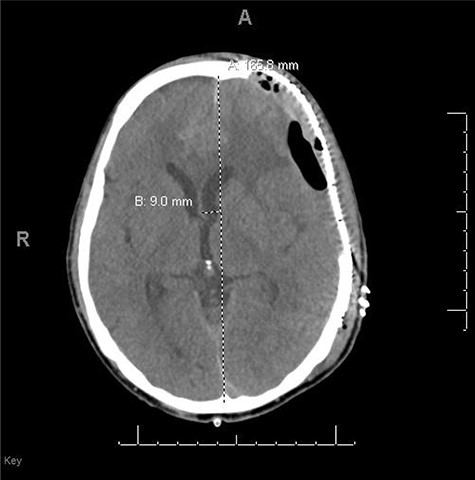

He had a significant recovery, to the point where he was awake with mild right paresis. He was following commands briskly but remained nonverbal. On hospital day 26, he developed neurological deterioration with decreased mental status and worsening right hemiparesis. Clinical examination noted pronounced new indentation of his hemicraniectomy flap site. CT head showed a rightward shift away from the craniectomy site and impending herniation (Fig. 4).

CT head POD26 from craniectomy demonstrating findings consistent with SSFS.

He was positioned in Trendelenburg position and infused with intravenous fluids with some improvement in his symptoms. Based on his clinical and radiographic picture, SSFS was suspected. He was taken to the operating room for an emergency left cranioplasty, with a preformed fronto-temporo-parietal titanium mesh.